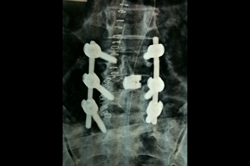

Spine